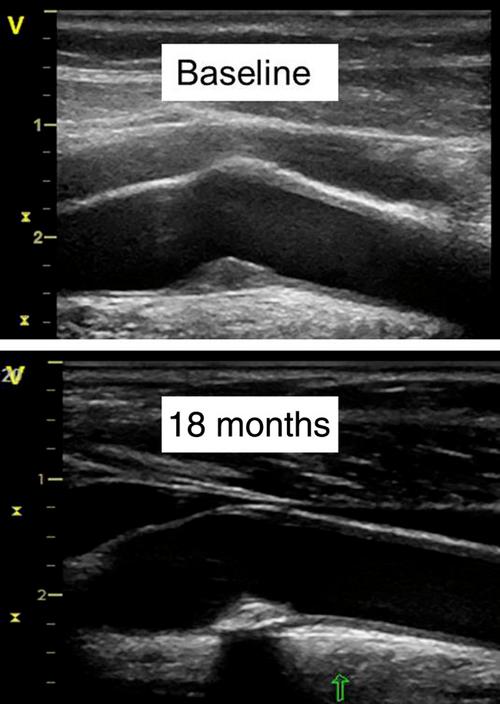

B超检查如何发现斑块?

B超检查通过高频声束穿透人体组织,利用不同组织对声波的反射和吸收特性形成图像,血管在B超下呈现为无回声的管状结构,而斑块由于内部成分不同(如脂质、纤维组织、钙化等)可表现为不同回声的异常结构,根据回声特点,斑块可分为低回声、等回声、强回声及混合回声等类型,B超检查不仅可以直观显示斑块的位置、大小、形态,还能通过彩色多普勒观察斑块的血流动力学改变,评估血管狭窄程度。